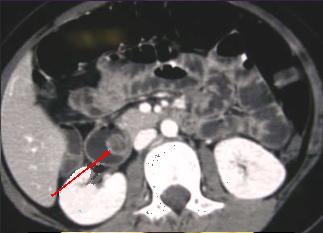

Lipome de

intestin grele : :Masse ovoide a bord lisse et

a hypodense de intestin . Image TDM en coupe coronal |